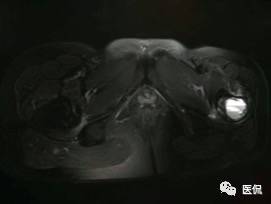

影像资料:

(3)MRI ABC的特征为鼓囊状的膨胀性破坏,呈单囊或由低信号的间隔分隔成大小不等的多囊。因血细胞和血浆的分离和沉淀,囊内可见液-液平面。在T2WI上,液面上层为高信号,下层为低信号;T1WI上则相反,上层为低信号,下层为偏高信号。液-液平面是ABC较特征的征象。增强检查低信号的纤维间隔呈环形强化。继发性动脉瘤样骨囊肿可在其原发病灶内有液-液平。

【诊断要点】发生于青少年长骨干骺端偏心膨胀的溶骨性病变,MRI检查病灶内见有液-液平征象时应首先考虑为动脉瘤样骨囊肿。